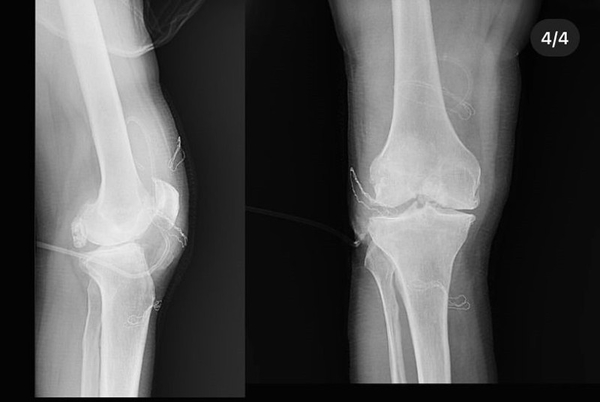

Diz ağrısı şikayeti ile geldiği Düzce Üniversitesi Tıp Fakültesi Hastanesi'nde ameliyata alınan hastanın dizlerinden toplam 41 adet multipl sinovial kondromatozisi çıkartıldı. Özellikle diz eklemi çevresinde görülmekle birlikte kalça, dirsek ve diğer eklemlerde de görülen, ufak parçalardan oluşan cisimler olarak tanımlanan eklem faresi, eklem çevresinde eklem sıvısı ya da sinoviyumda görülen kıkırdak ya da kemik parçalarıdır. Eklem farelerinin boyutları birkaç milimetreden birkaç santimetreye kadar çıkabiliyor.

Düzce Üniversitesi Tıp Fakültesi Hastanesi Ortopedi ve Travmatoloji Kliniği'nde başarılı geçen operasyonu; Doç. Dr. Zekeriya Okan Karaduman, Doç. Dr. Mehmet Arıcan ve Dr. Öğr. Üyesi Sönmez Sağlam gerçekleştirdi.